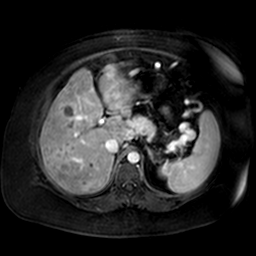

![]() |

| (a) | (b) | (c) | (d) |

Unsupervised Categorization: Our category discovery clusters are generally visually coherent within the cluster and size-balanced across clusters. However, image clusters formed only based on text information (of radiology reports) are highly unbalanced [49], with three clusters inhabiting the majority of images. Note that our method imposes no explicit constraint on the number of instances per cluster. Fig. 6 shows sample images and their top-10 associated key words from two randomly selected clusters (more results are provided in the supplementary material). The LDPO clusters are found to be clinically or semantically related to the corresponding key words, which describe presented anatomies, pathologies (e.g., adenopathy, mass), their associated attributes (e.g., bulky, frontal) and imaging protocols or properties.

The category discovery clusters employing our LDPO method are found to be more visually coherent and cluster-wise balanced in comparison to the results in [49] where clusters are formed only from text information ( radiology reports). Fig. 7 Left shows the image numbers for each cluster from the AlexNet-FC7-Topic setting. The numbers are uniformly distributed with a mean of 778 and standard deviation of 52. Fig. 7 Right illustrates the relation of clustering results derived from image cues or text reports [49]. Note that there is no instance-balance-per-cluster constraints in the LDPO clustering. The clusters in [49] are highly uneven: 3 clusters inhabit the majority of images. Fig. 6 shows sample images and top-10 associated key words from 5 randomly selected clusters (more results in the supplementary material). The LDPO clusters are found to be semantically or clinically related to the corresponding key words, containing the information of (likely appeared) anatomies, pathologies (e.g., adenopathy, mass), their attributes (e.g., bulky, frontal) and imaging protocols or properties.